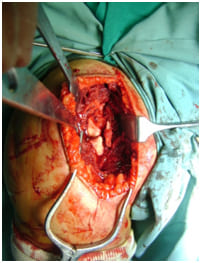

intra operative picture

Complex Shoulder Fractures are per se difficult, and do leave behind a residual disability if not done well. Therefore it is important for you to consult a shoulder expert!